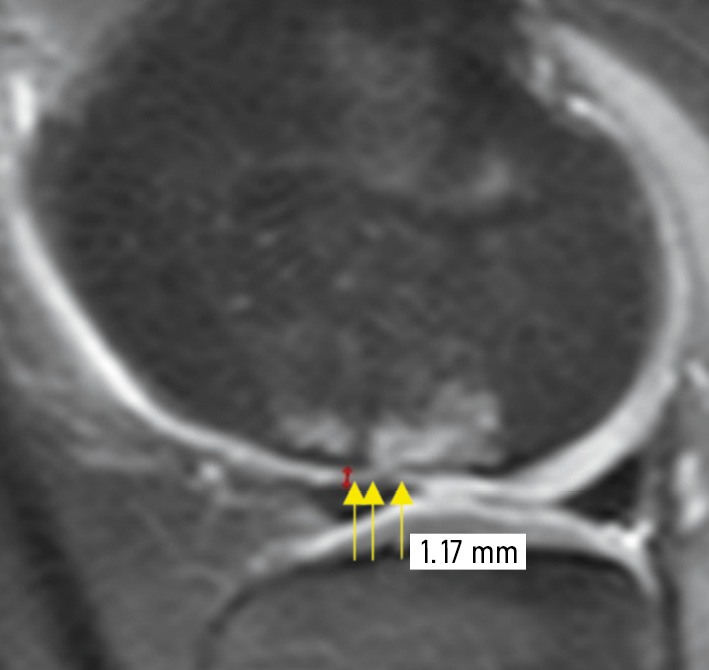

In Figure 4, thinning and hypointensity of the signal from the articular cartilage in the OD lesion are observed. The MRI shows a grade III cartilage damage, according to ICRS. The score was 30 points.

Fig. 4. Magnetic resonance imaging of the knee joint (sagittal PD-FS image) of a child with an osteochondritis dissecans lesion. Thinning and hypointensity of the signal from the articular cartilage in the OD lesion are observed. The magnetic resonance picture shows a grade III cartilage damage, according to ICRS